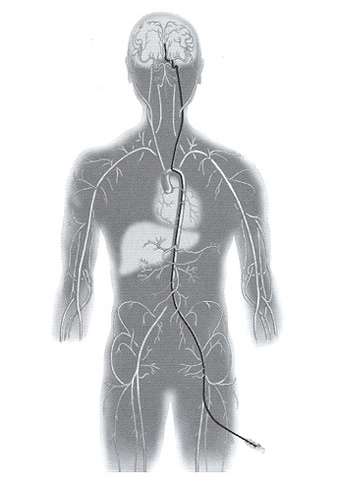

Endovascular occlusion of aneurysms includes the use of detachable coils. This is a angiographic procedure where a small soft catheter is introduced into the blood vessel from the leg artery. From there the catheter is carefully threaded up into the brain and the tip of the catheter is placed in the aneurysm (figure 6). Then through the catheter small soft coils are introduced into the aneurysm to block it completely (figure 7).

Figure 6. The catheter is carefully threaded up into the brain.